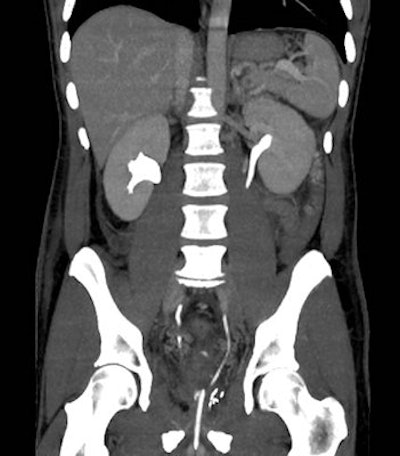

Image from a triple-bolus MDCT urography acquisition in a 45-year-old postoperative patient shows simultaneous imaging of arterial, parenchymal, and excretory phases. This technique combined with preliminary unenhanced scans can allow time- and dose-efficient, reliable investigation of suspected iatrogenic injuries, including assessment of extraluminal blood, abnormal collections, active bleeding, urinary extravasation, and venous patency. All images courtesy of Dr. Massimo Tonolini.Robot-assisted laparoscopic radical prostatectomy (RALRP) is now the preferred minimally invasive surgical treatment for localized prostate cancer, with optimal oncologic and functional results, but severe complications can occur in 5% to 7 % of patients and sometimes require more surgery. In hospitals with an active urologic surgical service, imaging is increasingly valuable for assessing suspected early complications following RALRP surgery, they explained.

MDCT studies should be complemented with multiplanar reformations and 3D volume-rendered images to effectively depict the postoperative anatomy and salient findings. To limit the radiation dose during multiphasic acquisitions, the researchers have developed split-bolus MDCT urography protocols that allow for combined renal vascular, parenchymal, and excretory acquisition.

MDCT urography protocol should include preliminary unenhanced scans, an initial 30 mL CM bolus injected at 2 mL/s flow for urinary opacification, a seven minute delay, a second (50 ml at 1.5 mL/s), and third (65 mL at 3 mL/s) CM injection separated by 20 seconds to provide parenchymal and vascular visualization respectively, followed by a single MDCT volumetric acquisition.

When performed properly, triple-bolus MDCT urography can provide simultaneous renovascular, corticomedullary, nephrographic, and excretory imaging with a reduced effective radiation dose compared to the usual multiphasic MDCT protocols, they stated.